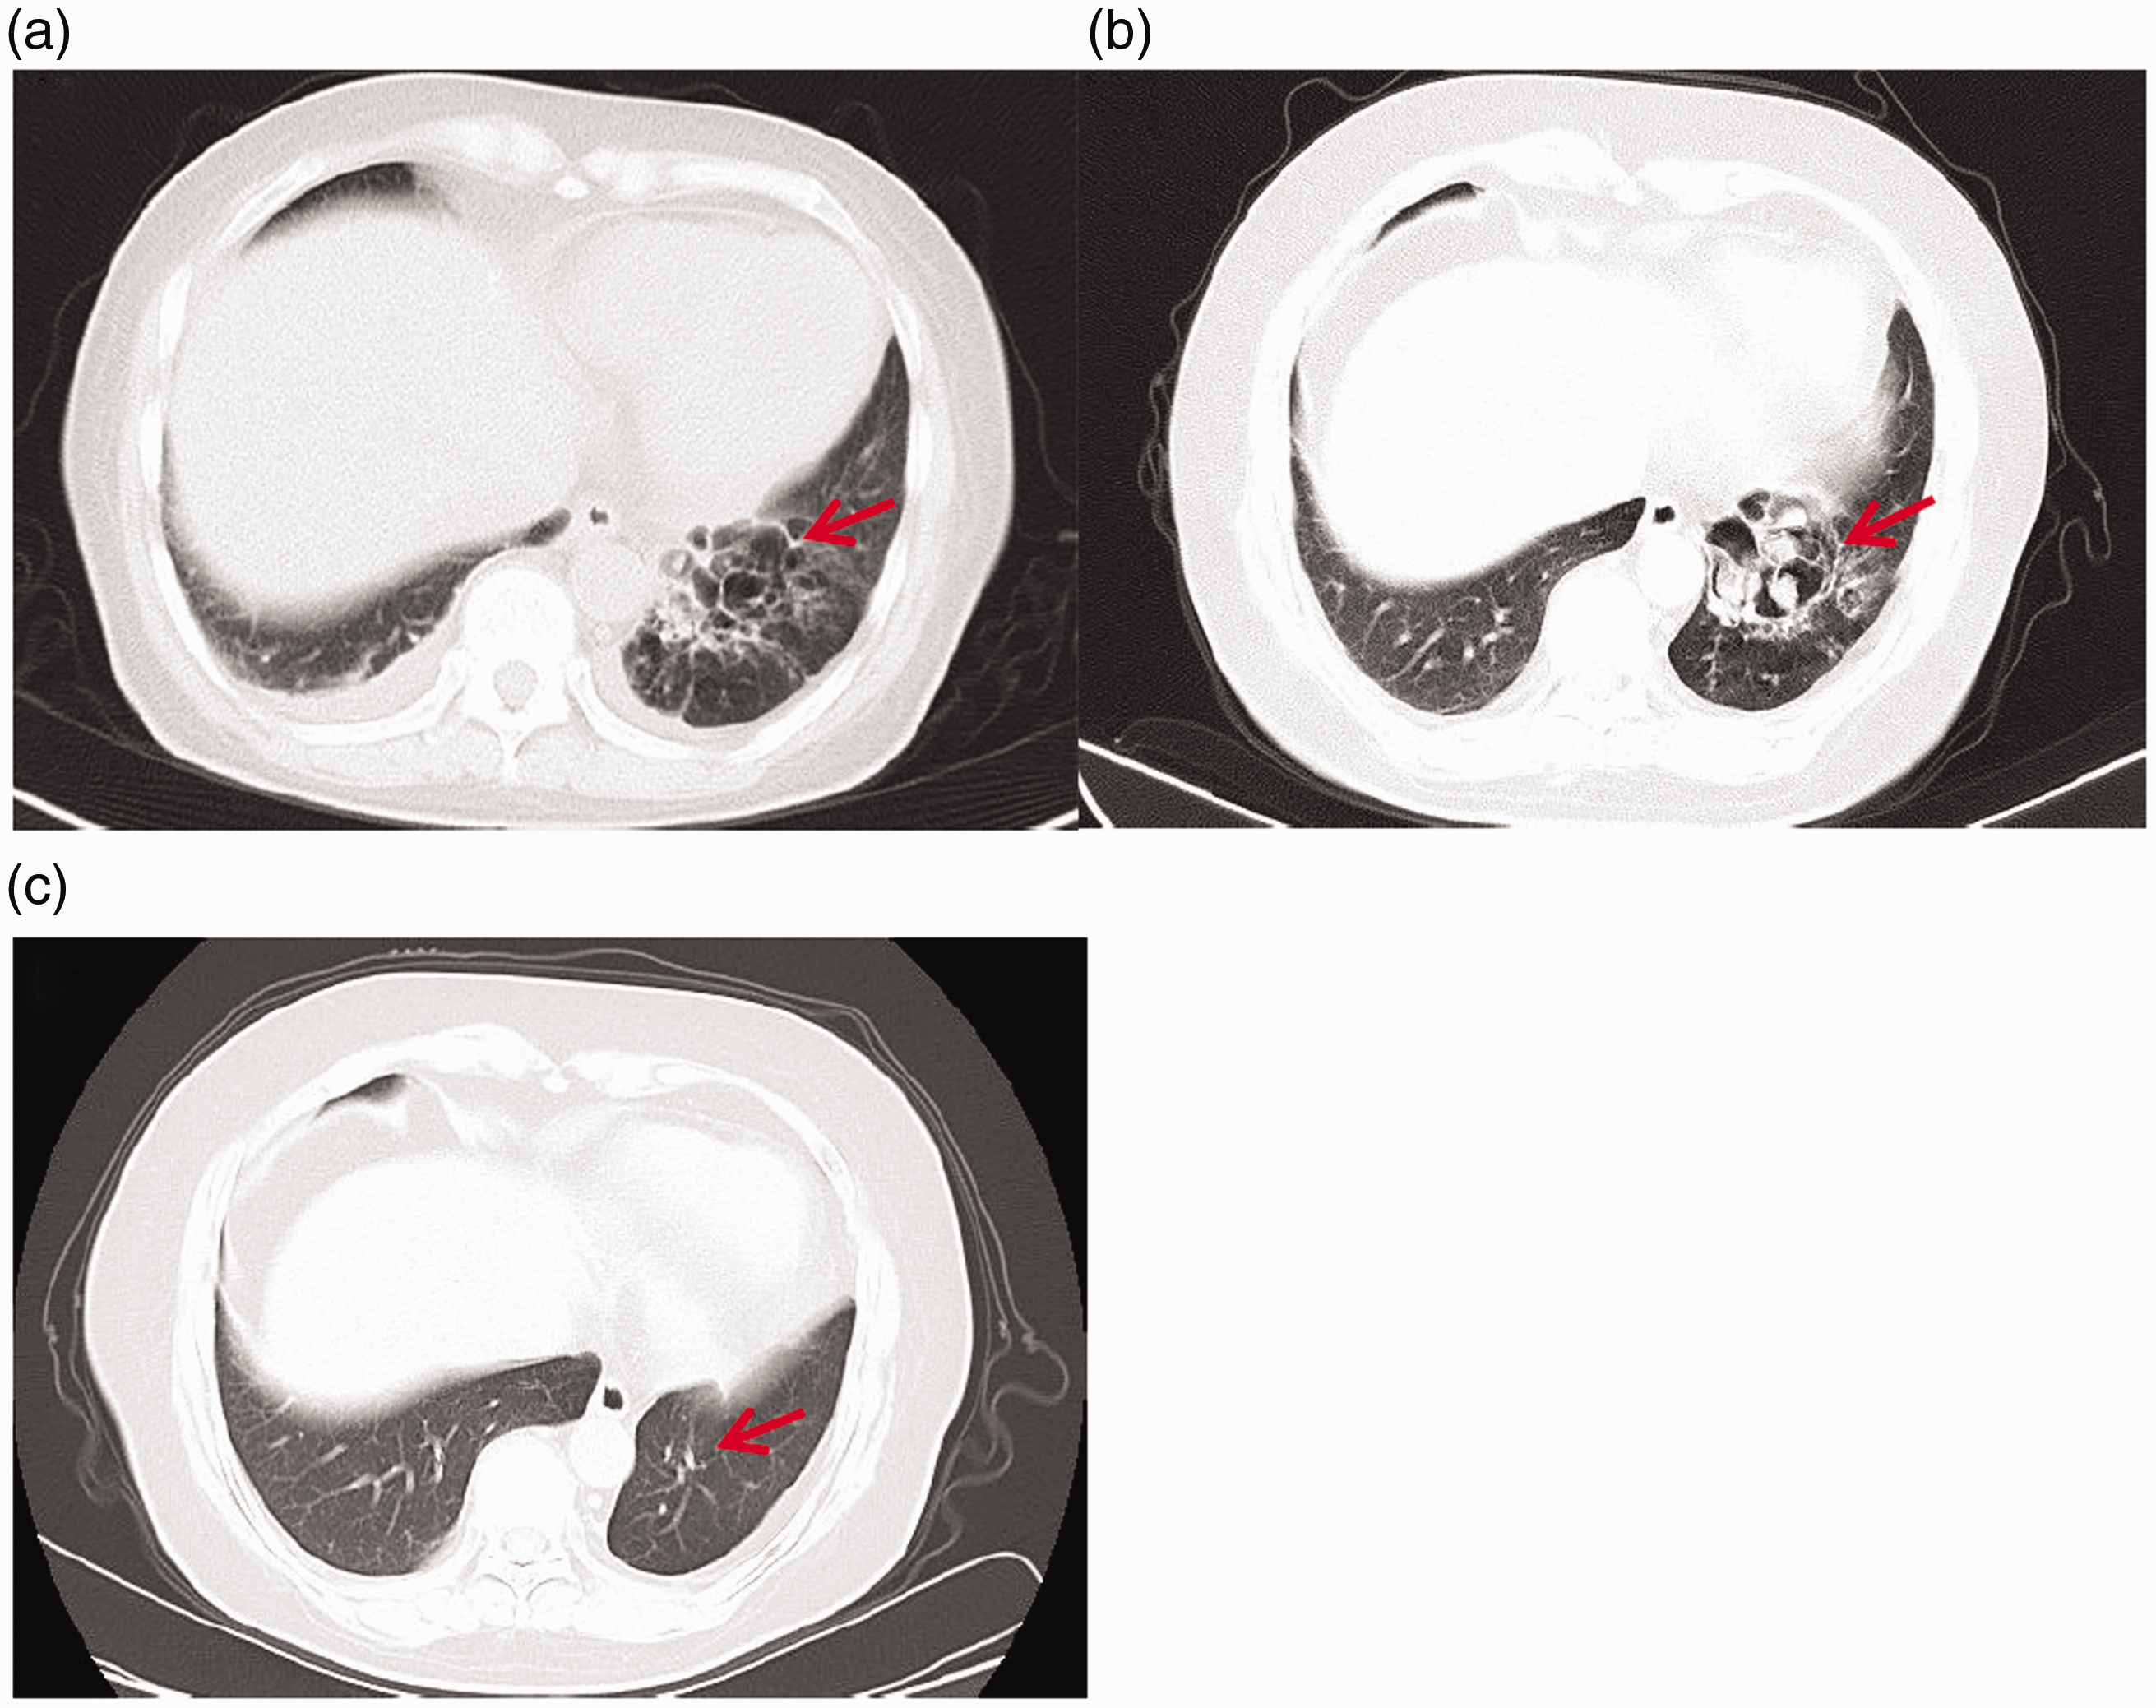

In August 2018, the patient was admitted to hospital with cough, expectoration, fatigue, headache, and edema of both lower limbs. Auxiliary examination revealed a 24-hour urine protein content of 2.44 g, creatinine levels of 432 µmol/L, albumin levels of 29 g/L, C3 of 0.36 g/L, ESR of 55 mm/hour, CRP levels of 136 mg/dL, and bronchiectasis. Infection in the lower lobe of the left lung was observed, with a suspected sputum thrombus or aspergilloma, and bilateral pleural effusion seen on a chest computed tomography (CT; Figure 1). Filamentous fungal growth was found in bronchoalveolar lavage fluid, and renal pathology was consistent with LN (class III and V lesions). A diagnosis of SLE with LN was made, as well as bacterial and fungal pulmonary infection with an SLEDAI score >15 points (lupus headache, 8 points; arthritis, 4 points; pleurisy, 4 points; proteinuria, 4 points; and skin rash, 2 points). Because SLE was in the severely active stage, methylprednisolone pulse therapy would ideally have been performed, but the patient could not tolerate large doses of corticosteroids and was suffering from pulmonary fungal infection, so was instead given an intravenous infusion of 40-mg methylprednisolone once daily and hydroxychloroquine 200 mg twice a day as immunomodulatory therapy, as well as voriconazole for the infection. After 2 weeks of anti-infective treatment, ESR and CRP levels were normal, C3 was 0.54 g/L, serum creatinine levels were 123 µmol/L, the 24-hour urine protein content was 0.59 g, the pulmonary infection was controlled, and the renal function was gradually recovering. The patient was discharged from hospital after stabilization with a discharge treatment plan to continue taking oral itraconazole as well as the immunomodulators prednisone (40 mg, once daily), hydroxychloroquine, and mycophenolate (0.75 g, twice a day).

Chest CT findings. (a) Aspergilloma was suspected in the lower lobe of the left lung in August 2018. (b) A nodule in the left lower lobe of the lung was thought to be a fungus ball in October 2020. (c) Post-surgery in January 2021. Red arrow shows lung lesions and pulmonary manifestations after resection.

After receiving informed consent of the patient, she underwent lobectomy of the lower left lobe under general anesthesia on November 12, 2020. The postoperative pathological result was pulmonary aspergillosis (Figure 2). To reduce the risk of infection, mycophenolate was stopped on the day of surgery and 2 weeks after the operation, and prednisone was reduced to 5 mg daily. Voriconazole anti-fungal therapy was continued post-surgery. C3 was re-examined after 2 weeks, showing an increase from 0.45 g/L to 0.78 g/L; serum creatinine levels decreased from 126 µmol/L to 108 µmol/L, the 24-hour urinary protein content decreased from 1.1 g to 0.59 g, and there was a gradual improvement in renal function and control of LN. In January 2021, a follow-up chest CT showed that lung lesions were greatly reduced, and fatigue symptoms had also greatly improved.